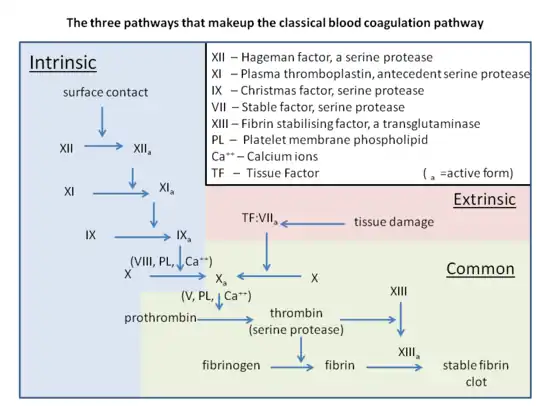

The variant causes elevated plasma prothrombin levels (hyperprothrombinemia),[4] possibly due to increased pre-mRNA stability.[5] Prothrombin is the precursor to thrombin, which plays a key role in causing blood to clot (blood coagulation). G20210A can thus contribute to a state of hypercoagulability, but not particularly with arterial thrombosis.[4] A 2006 meta-analysis showed only a 1.3-fold increased risk for coronary disease.[6] Deficiencies in the anticoagulants Protein C and Protein S further increase the risk five- to tenfold.[2] Behind non-O blood type[7] and factor V Leiden, prothrombin G20210A is one of the most common genetic risk factors for venous thromboembolism (VTE).[4] Increased production of prothrombin heightens the risk of blood clotting. Moreover, individuals who carry the mutation can pass it on to their offspring.[8]